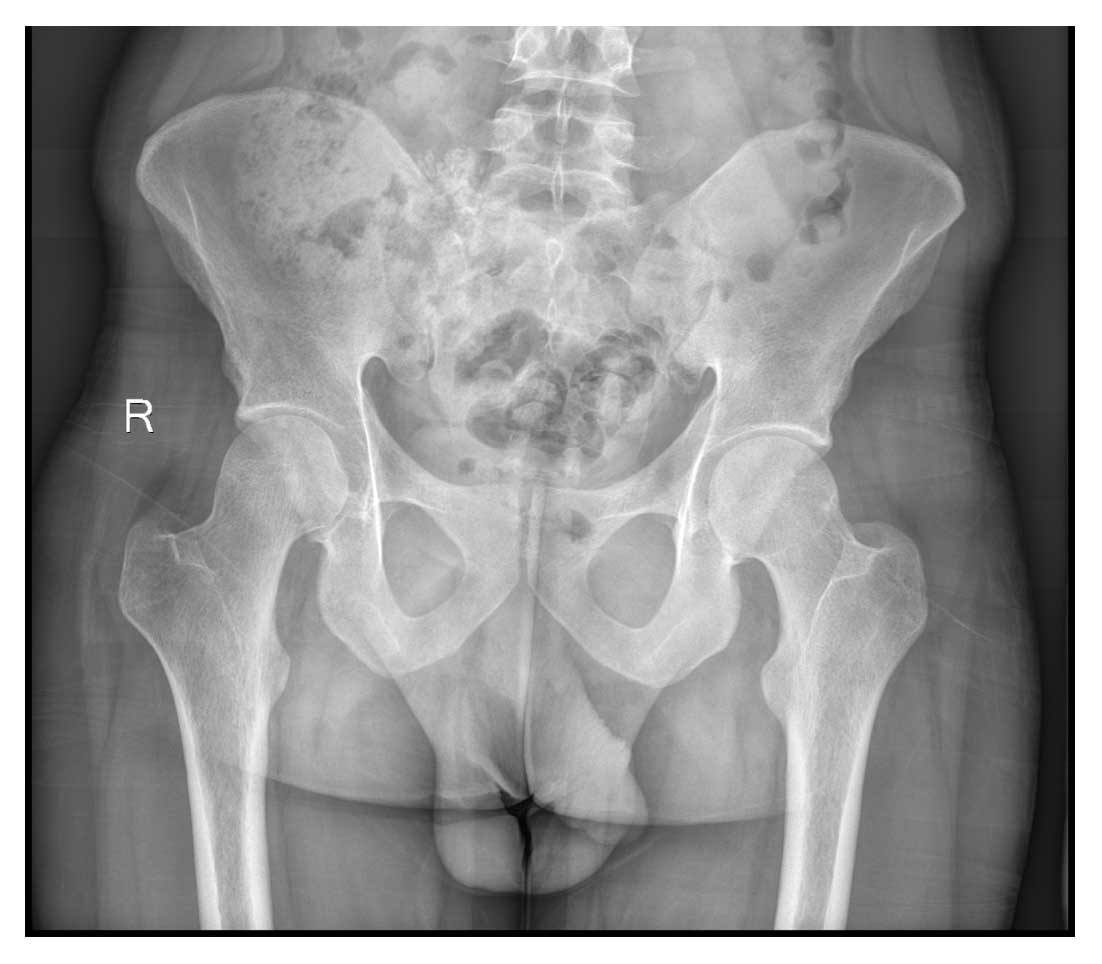

Ameliyat Öncesi: Röntgende sağ sakroiliak bölgede düzensizlik ve ossifikasyon görülmekte.